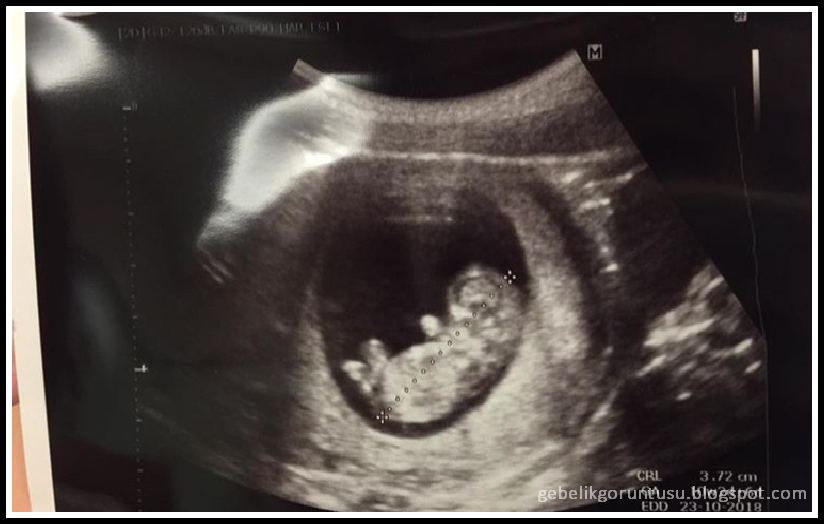

Mesela şimdi senin bebeğinin normal olup olmadığını bulalım. Bu haftanın genel olarak özeti bu şekilde. 10 haftalık bebek ultrason görüntüsü. 10 haftalık hamile olarak 2 ay 10 iki buçuk ay denilebilir günlük gebesiniz.

10 haftalık gebelik ultrason görüntüsünde artık bebeğini biraz daha iyi seçebilirsin.

10 haftalık gebelikte bebeğin kafa ile kalça arası yaklaşık 3 1 ila 4 2 cm ağırlığı 5 gram kadardır. Hamileliğin en zorlu ilk döneminin sonuna geliyorsun. Tırnaklar oluşmaya başladı erkek bebekte testestoron üretimi başlıyor kemik oluşumu başlıyor. Hafta hafta yapılan gebelik takibinde her haftada farklı ilerlemeler görülmektedir.

Hafta gebelik hafta hafta hamilelik resimli 10 haftalık hamilelik kaç aylıktır. 7 2 hafta 51 gün eder. On haftalık gebelikte bebeğin boyu yaklaşık 3 cm ağırlığı 4 gram kadardır. Haftasında bebek yaklaşık 3 4 cm ve boylarında olacaktır.